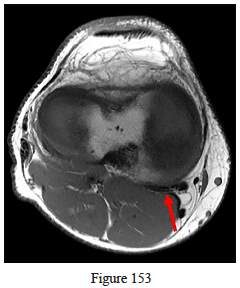

153. Which structure is identified byt he arrow in Figure 153?